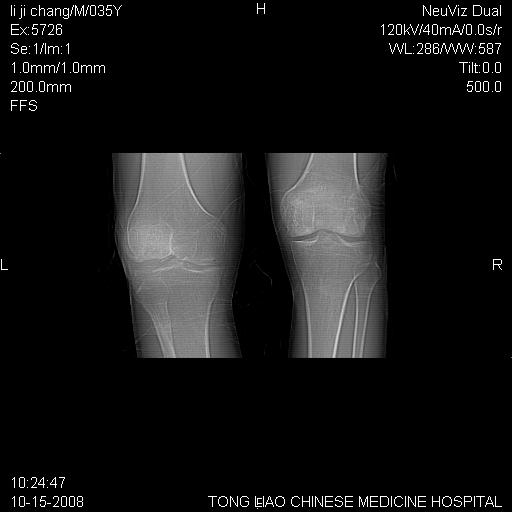

男,35岁,骨科诊断骨性关节炎。继往使用过激素,现股骨头坏死。膝关节病变,请会诊

一元论-----亦考虑为坏死

支持考虑无菌坏死

支持无菌坏死伴退行性骨关节病.

剥脱性骨软骨炎:是一种关节下软骨及软骨下骨缺血性坏死。

支持 无菌性坏死伴退行性骨关节病。